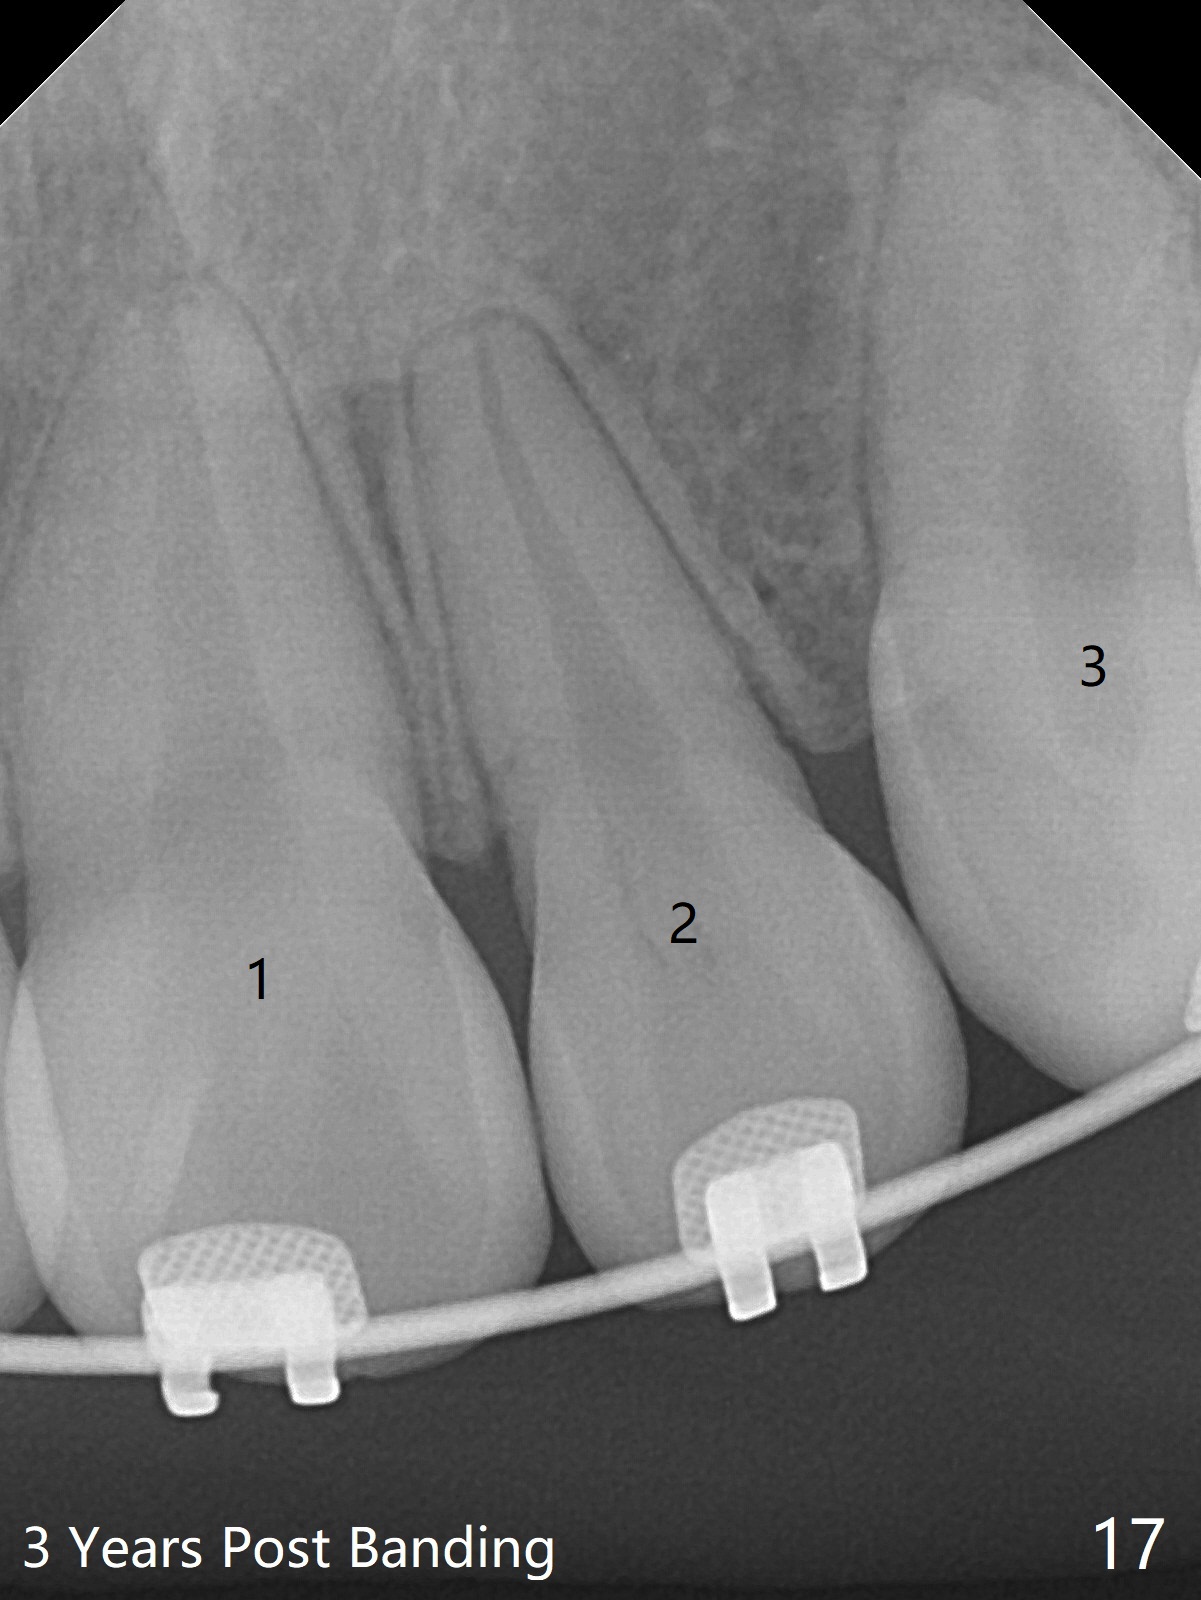

Thirteen months post banding, U dental midline apparently coincides with facial one, diastemata: UL2/3, UL6/7, L3-3, UL post detached, placed crimpable mini post mesial to UL2, closed spring UL2-7. Three-4 weeks later, diastema appears between UL1/2, while that of UL6/7 closes. Continue closed spring between UL2/7, while adding power chains U2-2 (Fig.12). To correct anterior overjet (Fig.13), Class II retraction is introduced bilaterally (Fig.14). After mesialization of LL3 (with Class I canine occlusion), L3-3 are being ligated as an anchor to mesialize LL5 (Fig.15). Occlusion appears to be Class II nearly 3 years post banding. Miniimplants are planned to distalize the upper dentition. Upper anterior PAs are taken to determine whether the roots of the upper anterior teeth have been resorbed. In fact, they are (Fig.16,17). Fortunately the anterior overjet does not look so severe. Orthodontic treatment should be terminated soon. Next case PAs should be taken prior to distalization.